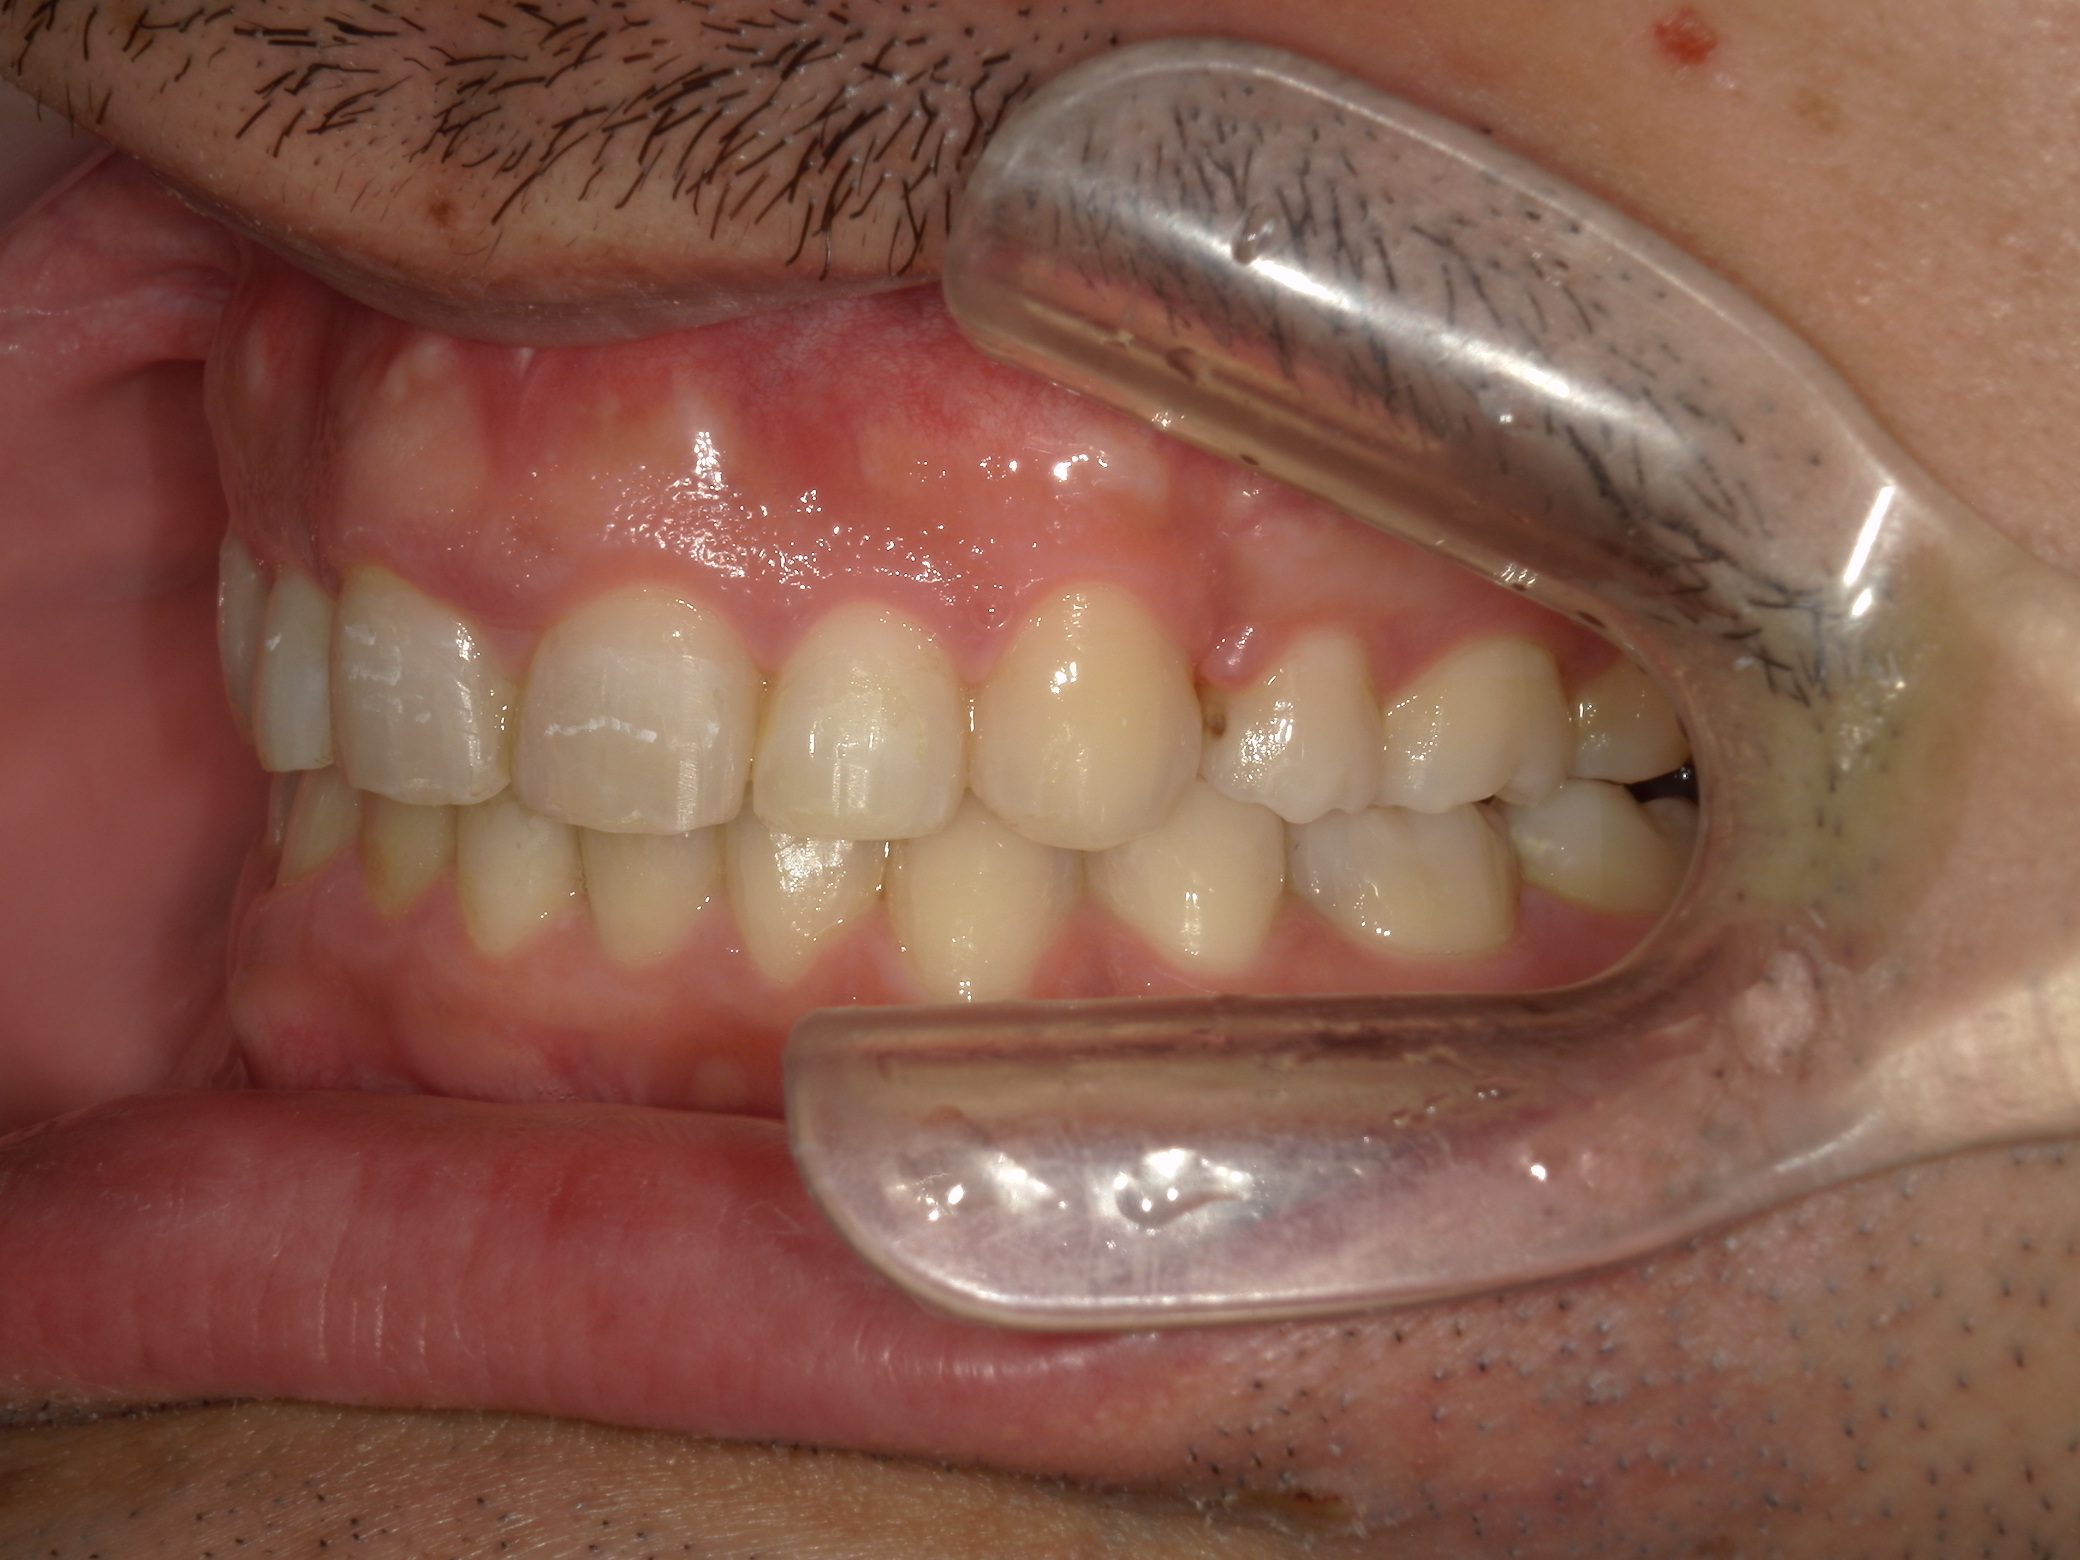

全顎ワイヤー矯正 症例(79)

主訴: 前歯が噛み合わない。歯並びが気になる。

上下左右 第一小臼歯(4本)、上下右 親不知(2本)抜歯。

ミニインプラント、アップライトスプリングを併用。

| 治療期間 | 3年7ヶ月 |

カテゴリー : ガタガタ(叢生) , 噛み合わせが深い(過蓋咬合)